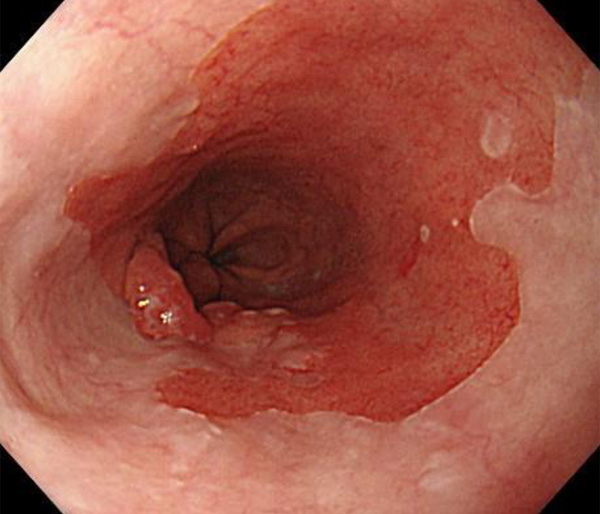

内視鏡所見と病理組織像の1対1対応が可能な症例を公募いたします。主にLSBEに発生した早期癌(HGDを含む)を対象としますが、興味深い症例であればSSBE癌でも結構です。採否は世話人へご一任ください。

症例呈示希望者は応募用紙に記入の上、代表的な内視鏡(2枚)、切除標本(新鮮、固定)、切り出し図、マッピング、代表的組織像とともに、Barrett 食道研究会事務局 barrett.shinshu@gmail.comへお申し込み下さい(10MB以下でお願い致します)。

特に、本邦では極めて稀なlong segment Barrett’s esophagus(LSBE)から発生した早期癌は、診断に難渋する場合も多く、欧米ではランダム生検による検出が標準的とされています。背景のBarrett食道もろとも全体を内視鏡切除+ラジオ波焼灼する欧米と異なり、ESDで内視鏡的な局所切除が基本の本邦では、存在診断+範囲診断(特に水平)を的確に行うことが不可欠です。

そのためには、一流の病理医による組織学的診断とエキスパート内視鏡医による拡大内視鏡像との一対一対応を徹底的に行うことで、『本来、見えないであろう拡大所見の先にある組織構築像が診えてくる』所まで内視鏡診断レベルを上げていく必要があります。その実現には、一対一対応を追究した症例(特にLSBE発生例)1例でも多く経験するしかありません。本研究会でBarrett食道腺癌(LSBE発生早期病変)を共に学び、拡大内視鏡像の一歩先を診るスキルを習得しましょう!一人でも多くの皆様のご参加をお待ちしています。